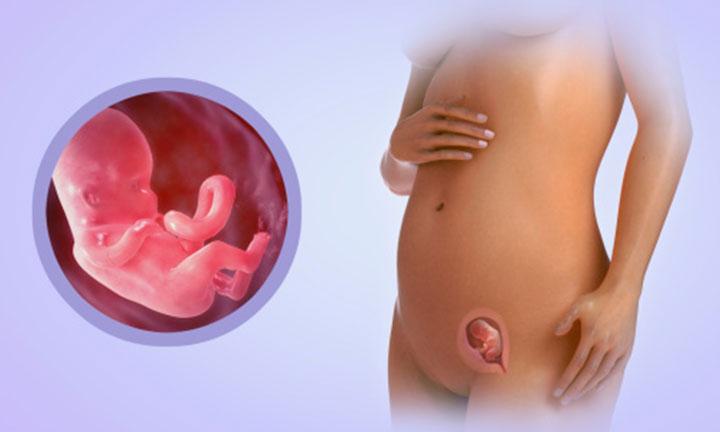

Этапы развития эмбриона человека: 14 недель